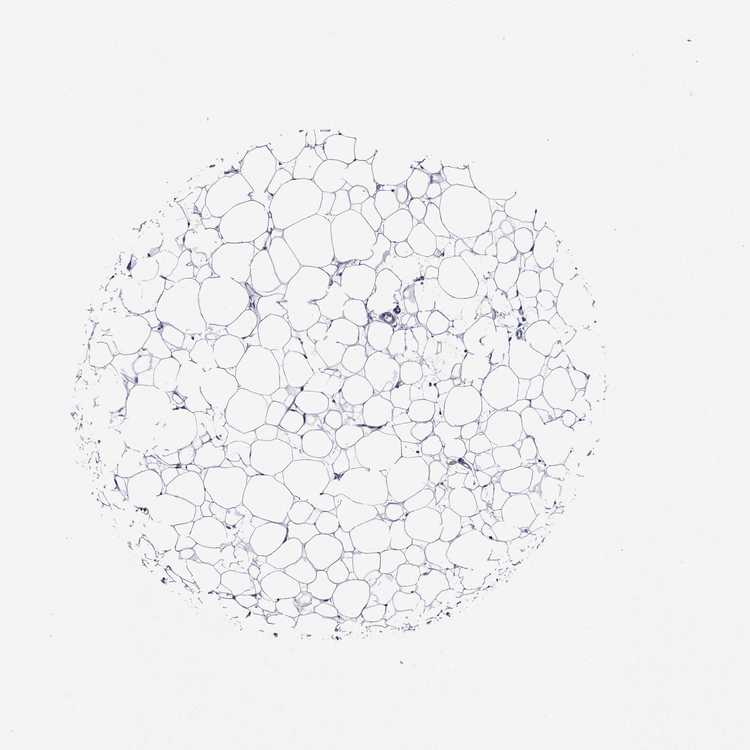

TISSUE PRIMARY DATA BREAST Show tissue menu

Breast

BREAST - Antibody stainingi

Antibody staining in the annotated cell types in the current human tissue is reported as not detected, low, medium, or high, based on conventional immunohistochemistry profiling in selected tissues. This score is based on the combination of the staining intensity and fraction of stained cells.

Each image is clickable and will lead to virtual microscopy that enables deeper exploration of all samples and also displays staining intensity scores, fraction scores and subcellular localization as well as patient and tissue information for each sample.

Antibody HPA041806Antibody HPA046289Antibody HPA075094

Adipocytes Not detectedNot detectedNot detected

Glandular cells MediumMediumNot detected

Myoepithelial cells LowMediumNot detected